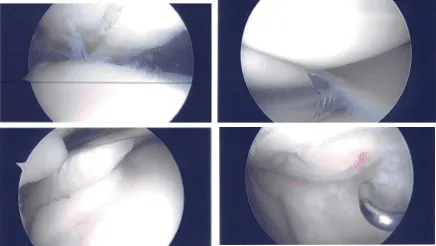

An Esmarch was applied, and tourniquet was raised to 325 mmHg. A lateral entry portal was made for the knee scope and the scope was entered. The patellofemoral joint was intact. The scope was moved to the medial compartment. Fraying of the medial meniscus was seen.

A medial entry portal was made using a spinal needle. The medial meniscus tear was excised using a straight biter and shaver. The scope was moved to the intercondylar notch where an ACL was intact. It was moved to the lateral femoral fraying of the medial margin of the lateral meniscus also.

The shaver and straight biters were used on the medial margin of lateral meniscus to a balanced margin. The scope was again moved to the patellofemoral joint where the fracture was seen and found to be displaced. The fracture was cleaned and an osteotome was used to release the fracture from the arthroscopic portal.

Intraoperative Arthroscopy Images

Now, the knee was put in extension and an anterior midline vertical incision was given to expose the fracture. With sharp dissection, the bone was reached. The lateral flap of the tendon was raised over the patella. The fracture site was reached which was mobile.

The fracture was reduced back and held with clamps. The two K-wires were passed. C-arm was introduced and checked and found to be acceptable reduction; 2 cannulated cancellous screws were inserted for fixation and compression.

The arthroscope was inserted to check the reduction and found to be appropriate. There was some cartilage damage around the edge which was debrided. Hemostasis was achieved. Closure was performed in layers after the closure of the quadriceps tendon and the paratenon.